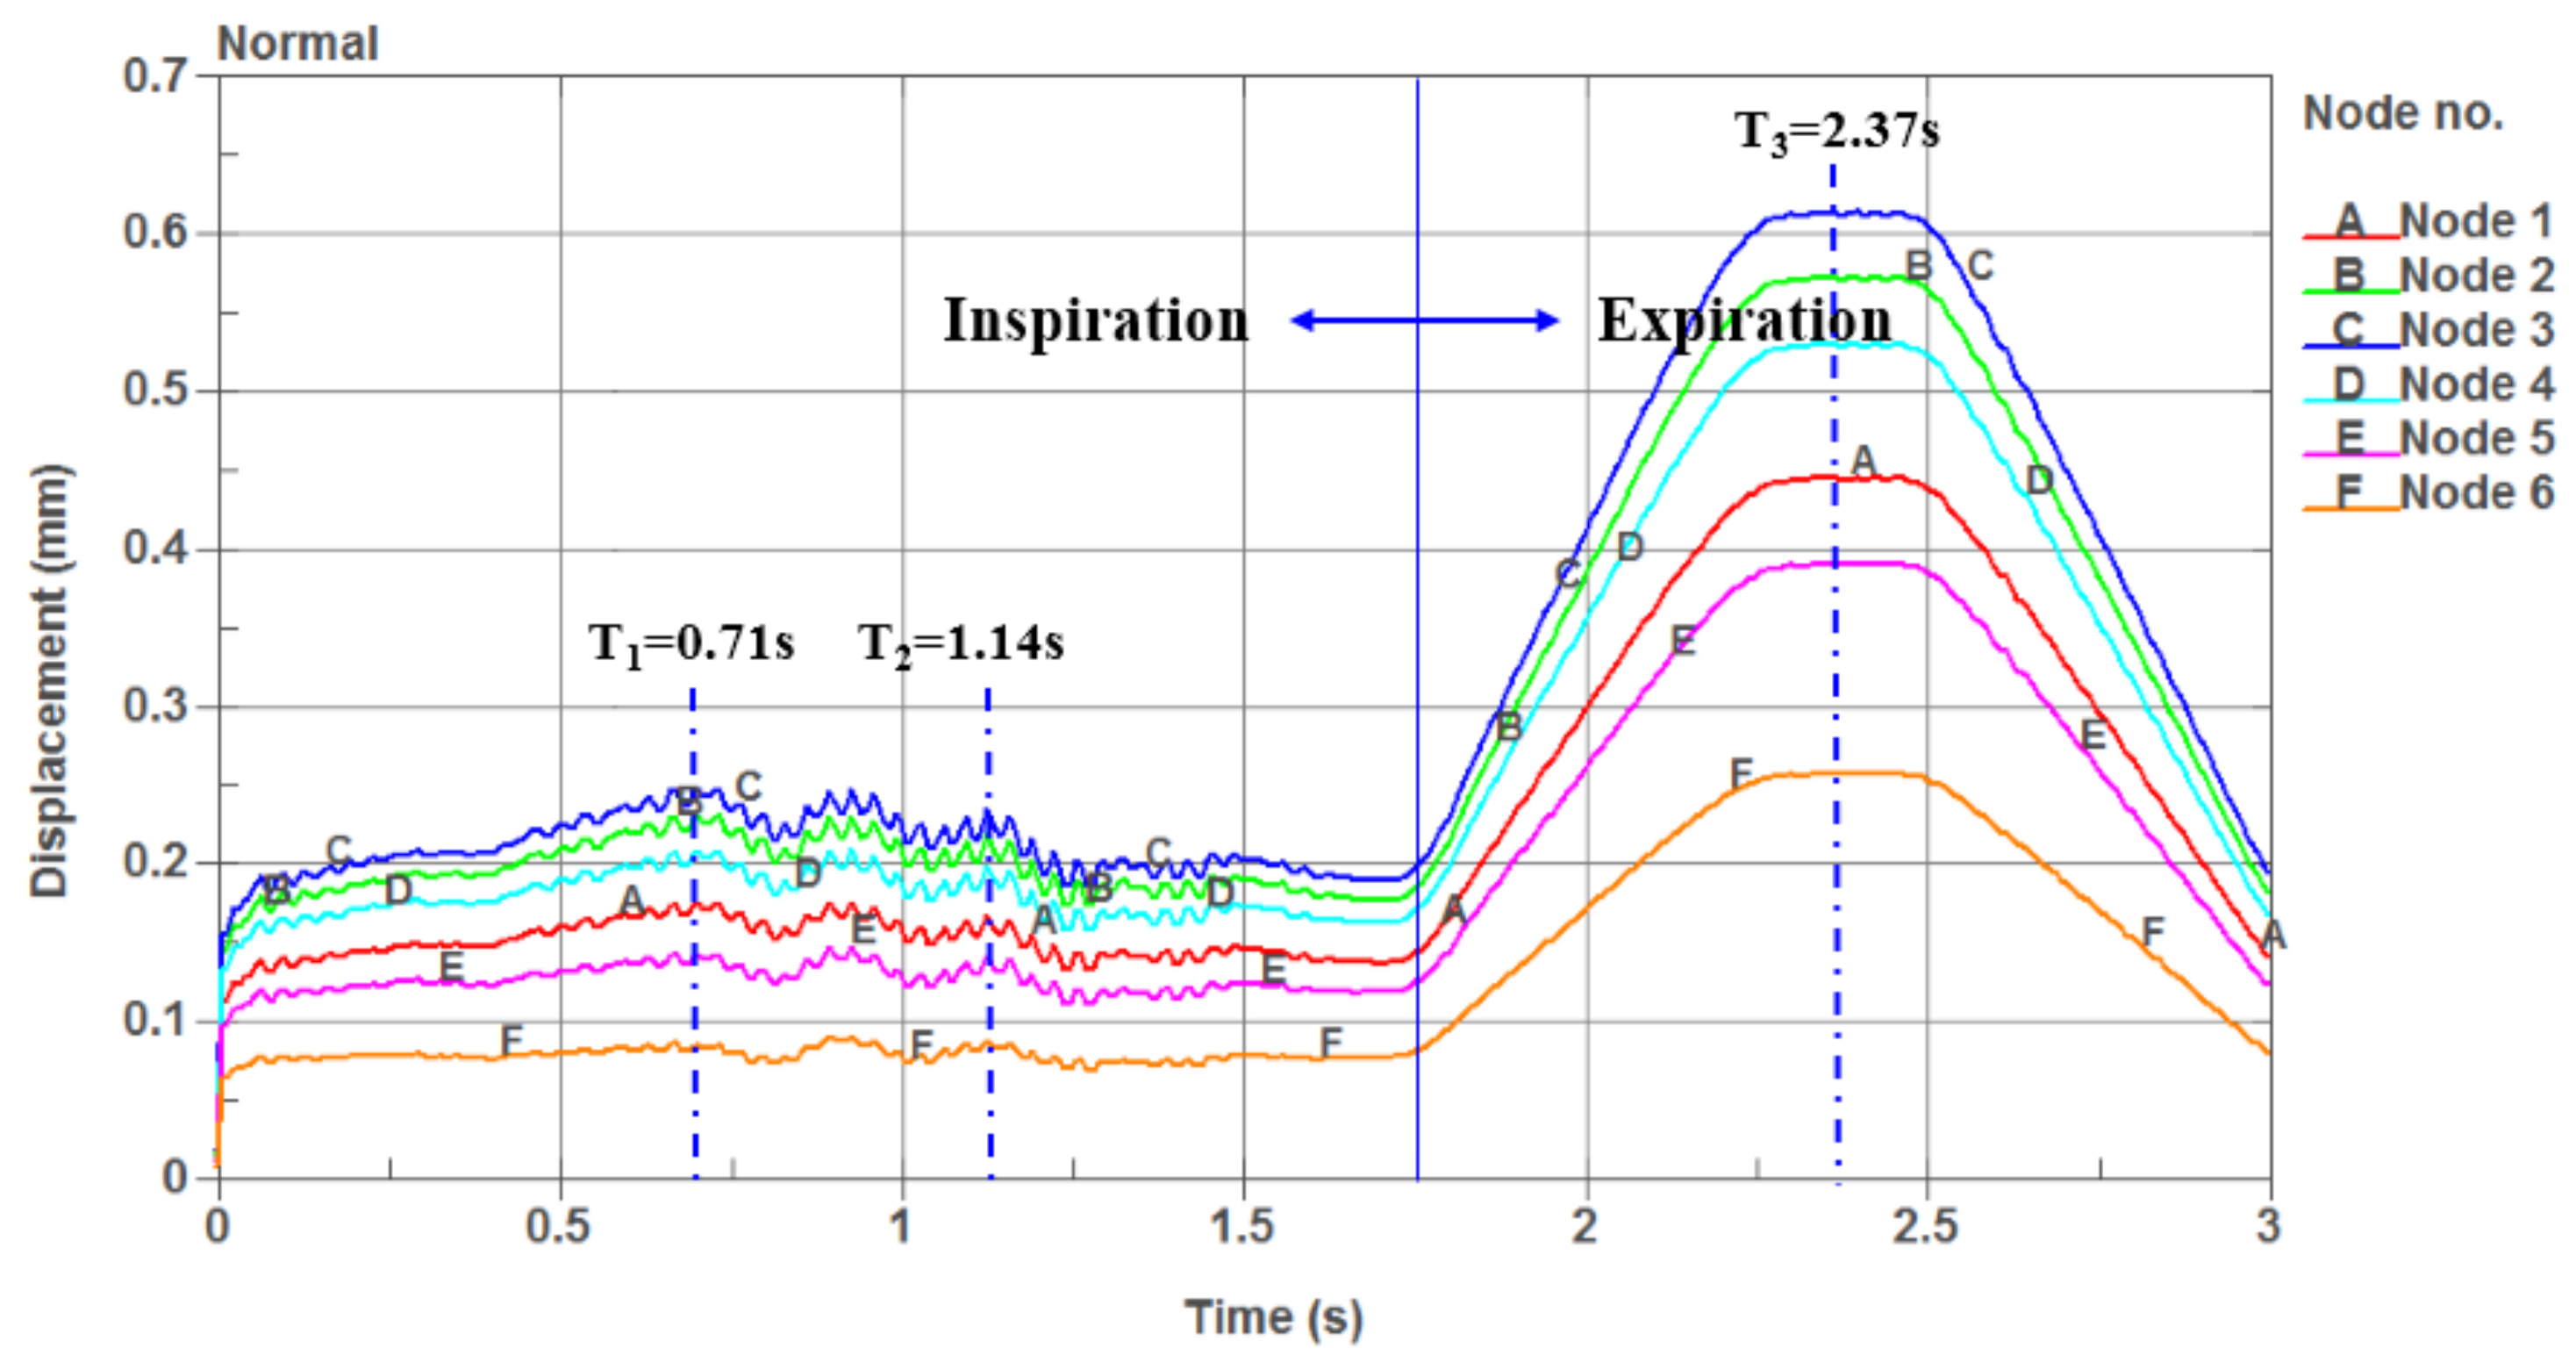

3.1. One-Way Valve Effect of Soft Palate

- The airflow characteristics during the inhalation phase are noticeably different from those in the exhalation phase for both eupnea and apnea. As the OSAHS patient breathes, the minimum pressure occurs alternately between the soft palate and the anteroposterior wall of pharynx, which causes the soft palate to vibrate during respiration, and therefore, the patient snores in sleep.

- The soft palate in pharyngeal cavity would exerts a one-way valve effect and collapses in the exhalation phase if the patient sleeps in the supine position, regardless of eupnea or apnea.

- The mechanical environment of the airway is directly dependent on the action of the airflow. If the mechanical properties of the soft palate remain unchanged, the pressure makes the soft palate collapse in apnea. In eupnea, the pressure allows the airflow to pass freely through the airway.